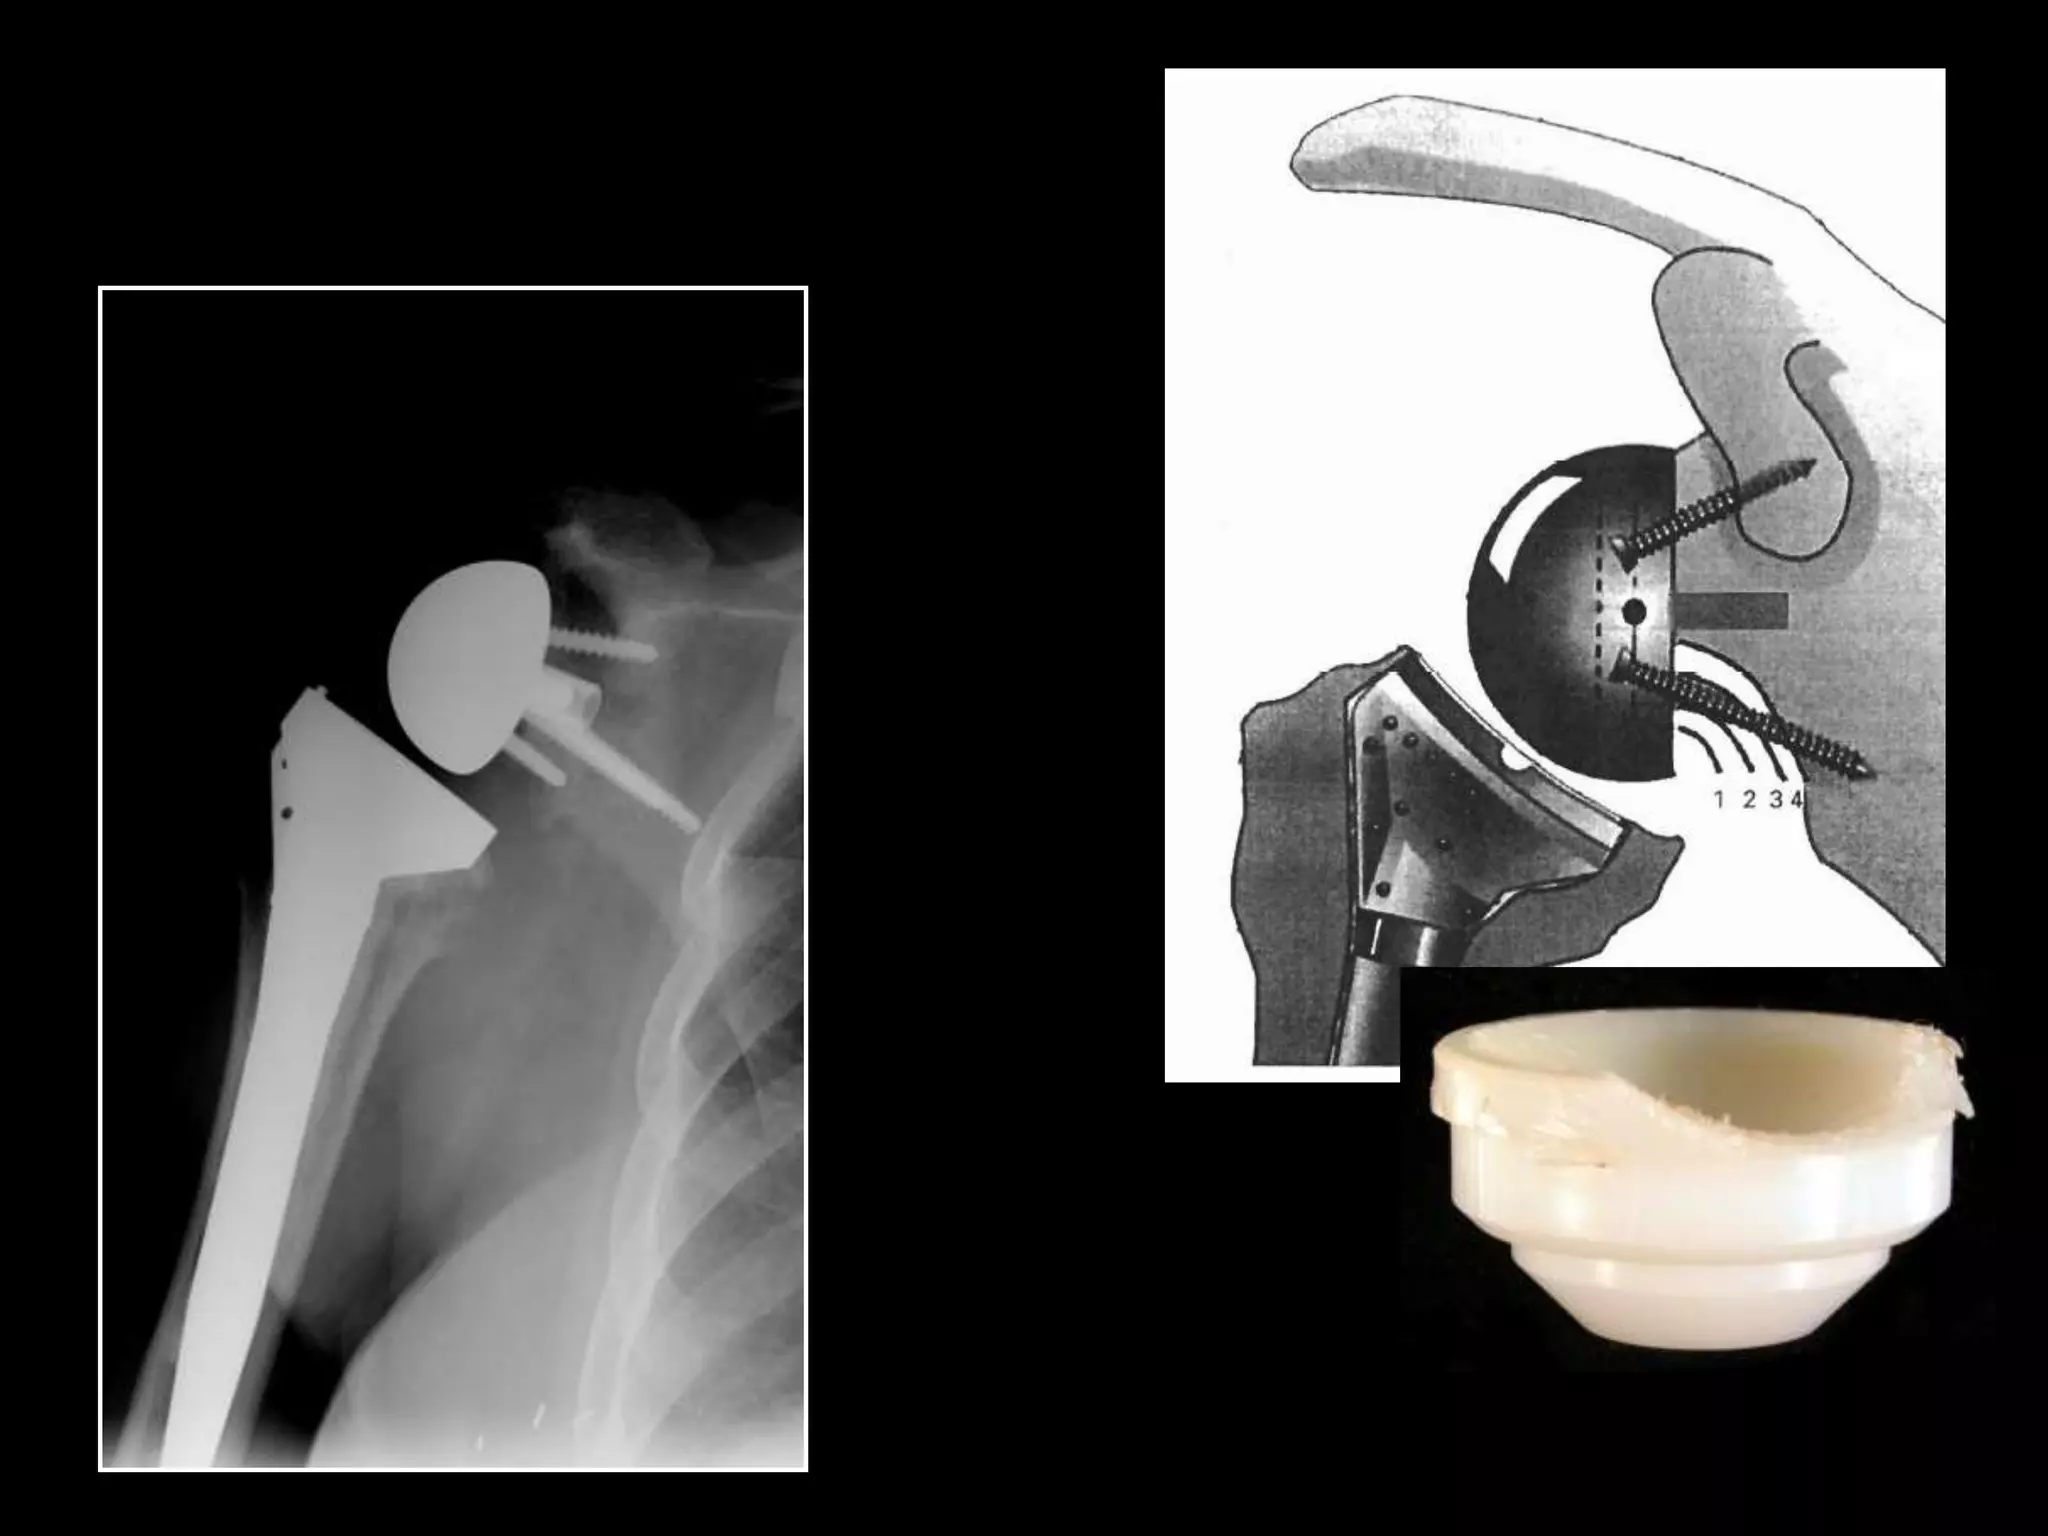

Grammont Type Reverse

(France 1987)

Grammont P, Trouilloud P, Laffay JP, et al. Etude et realisation d’unenouvelle

prothe`sed’e`paule.Rheumatologie. 1987;39:407–418. [French]

Grammont Type Reverse (France1987) Grammont P, Trouilloud P, Laffay JP, et al. Etude et realisation d’unenouvelle prothe`sed’e`paule.Rheumatologie. 1987;39:407–418. [French]